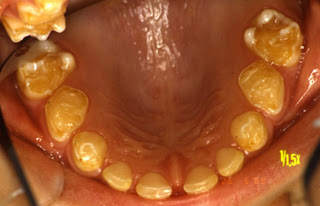

I dag var jeg hos tannlegen, det viste seg at jeg trenger mer enn en time. Men jeg fortalte tannlegen om quizzen, så han gav meg en estimert pris...

Resultatet er som følger: Jeg må trekke to tenner (visdomstenner( Yea-right)), opperere ut en tann (visdomstann) og jeg har to hull.

Han sa ingenting om Cola, men nevte at det ellers så greit ut... Regningen vil totalt komme på ca 6000 kroner.

Så det betyr at Tom vant, han vil motta premien (Tre visdomstenner) i løpet av noen uker.

I skikkelig nøttestil har jeg en nøtt dere kan knekke. Jeg har bestilt en time hos tannlegen, det er ca 7 år siden jeg var til en sjekk sist. Det var i militæret, da hadde jeg et par hull og to visdomstenner som de ikke rakk å gjøre noe med før jeg ble satt fri.Så her er årets nøtter:

Hvor mange hull tror du jeg har i tennene?

Hva tror du regningen vil komme på?

Vil tannlegen anbefale meg å drikke mer eller mindre cola, eller ingen av delene?

Det er ikke mine tenner det er bilde av!